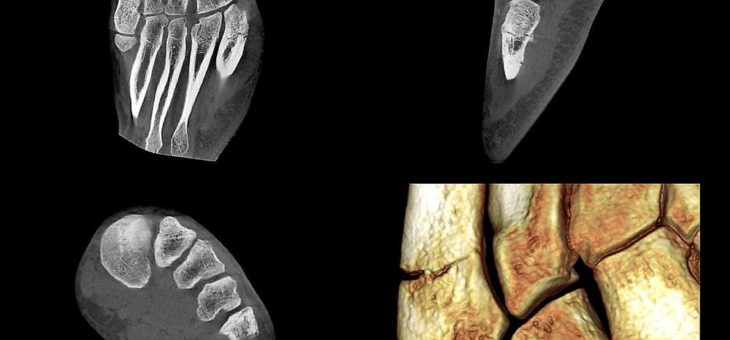

Perspektive DVT – „Die präzise Qualitätskontrolle optimiert die Endoprothetik“

„Mit der SCS Bildgebung habe ich nun auch in der bildgebenden Diagnostik eine ganzheitliche Lösung für meine Spezialisierung.“ Im Gelenkzentrum von Herrn Prof. Dr. med. habil. Tim Rose haben Patienten die Möglichkeit, sich hochspezialisiert behandeln zu lassen. Der Facharzt für Orthopädie und Unfallchirurgie, mit Zusatzbezeichnung Sportmedizin, blickt inzwischen auf 20 Jahre Berufserfahrung und mehr alsRead more about Perspektive DVT – „Die präzise Qualitätskontrolle optimiert die Endoprothetik“[…]